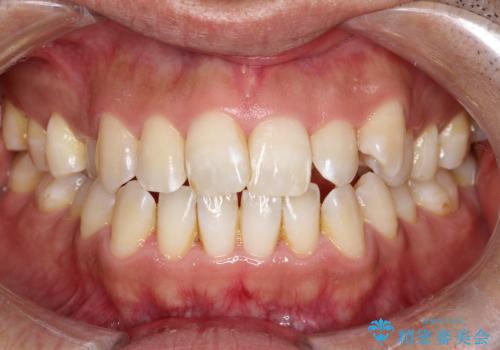

- 前歯の凸凹を主訴に来院されました。

インビザライン にて治療を行い、歯並びが綺麗になったと満足していただきました。

前歯のガタガタの量が多かったため、IPR(歯のサイズを小さくするための処置)を行なって治療しました。